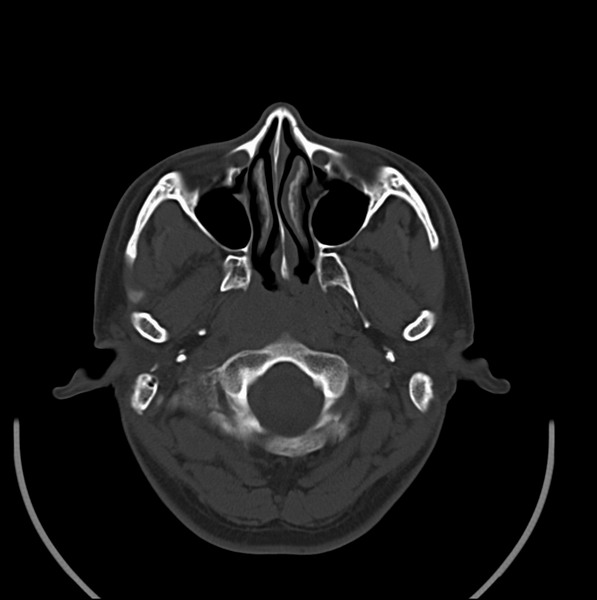

扫描示鼻咽腔不对称,中度狭窄,右侧咽隐窝消失,局部软组织肿块,鼻咽右侧壁增厚形成肿块,突入鼻咽腔,肿块平扫呈等密度,肿块向深部侵润,右侧翼内外肌受侵,右侧咽旁间隙变窄;向后生长,头长肌界线欠清,向后上生长侵犯同侧颈动脉鞘区。双侧海绵窦增宽,内见软组织影与鼻咽部肿块相连。考虑鼻咽癌。鼻咽癌主要是放射治疗,且效果较好;到当地有治疗设备较大医院治疗即可。

典型鼻咽癌侵犯右侧海绵窦(对放疗敏感)

还是先确诊,如果是鼻咽癌,一般行放射治疗;这例患者我首先考虑鼻咽癌